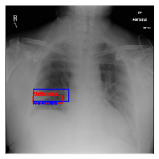

IV-D Investigation of the generated heatmap

By using the training result of the Adaptive DBN, the heatmap images were generated in addition to detection of B-Box. The heatmaps in Fig. 10 to Fig. 14 show the detection result of B-Box and the generated heatmap for some images. The red and blue rectangles in the image are given B-Box and detected B-Box, respectively. A heatmap is represented by the continuous value of range [0,255]0255[0,255], where the color map is jet color array (red means high value, while blue means small value). The diseases for detected B-Boxes in Fig. 10 to Fig. 14 were as follows; Infiltration (Fig. 10), Mass (Fig. 10), Nodule (Fig. 10), Mass and Pneumothorax (Fig. 10), Atelectasis (Fig. 14), Infiltration (Fig. 14), Atelectasis (Fig. 14), Atelectasis (Fig. 14).

Overall, the red area of the generated heatmap included in both the given B-Box and detected B-Box. On the other hand, the blue or yellow areas didn’t include in these B-Boxes. This tendency was seen in not only large diseases (e.g. Cardiomegaly or Infiltration) such as Fig. 10, but also small diseases (e.g. Mass or Nodule) such as Fig. 10. We consider that the experimental results caused by the discrete heatmap with binary output of final RBM layer instead of continuous heatmap. As a result, the red regions represents localization with strong relation to diseases and blue regions represents localization with weak relation. The generated heatmap shows the portion with strong relation more clearly.

In Fig. 14, the detected B-Box was located at a little upper than the given B-Box. The red area of the heatmap was also at upper position. The detected B-Box is slightly larger than the given B-Box. The detected B-Boxes are almost same as the given B-Boxes except the different size. For better detection capability, the feature of the generated heatmap will be investigated with the medical specialists.